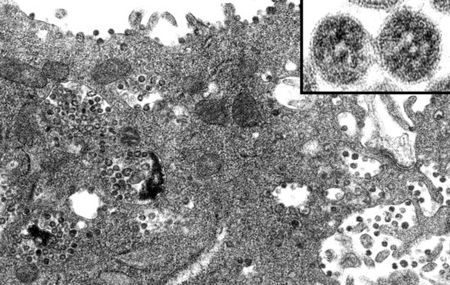

La Nuclear Threat Initiative aveva previsto tutto: “a maggio 2022 inizierà una nuova pandemia”

Nell’articolo de L’Antidiplomatico Davide Malacaria ci racconta di come, in un’esercitazione del 2021, l’organizzazione Nuclear Threat Initiative abbia simulato una pandemia di vaiolo delle scimmie che sarebbe iniziata il 15 maggio 2022. L’articolo de l’Antidplomatico usa termini come “profezia”, perché è con quelli che si trasforma quella che è una coincidenza in qualcosa di più maligno.